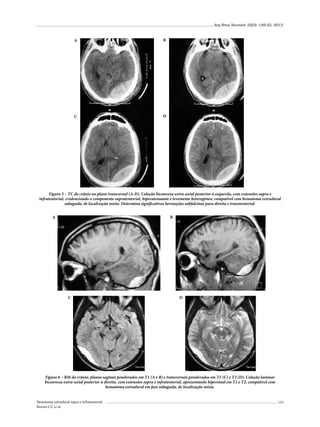

Portanto, do total de 182 casos de FEC, 115 crianças

foram do sexo masculino (63%) e 67 do sexo feminino

(37%) (Tabela 3).4,19,21,25-30,33-37

Tabela 2 – Prevalência (%) de FEC nas fraturas

de crânio (revisão bibliográfica)

Autor (ano)

Arseni e Simionescu (1966)

%

0,03

Matson (1969)